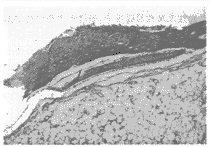

所有动物伤口I期愈合,无感染和窦道形成。肌肉内植入实验组织学观察3周时未见炎性细胞聚集及肌肉坏死,12周材料开始降解,36周时材料植入区部分被网状结缔组织和少许纤维肉芽组织修复,有少许中性粒细胞和巨噬细胞浸润,未见多核巨细胞。骨内长期植入实验X线摄片见6周时骨折愈合,无畸形(图1)。材料在12周前可清晰显影。组织学观察3周时骨折端有明显骨痂生成,材料在髁部与骨组织直接接触,在髓腔中材料周围有明显新骨生成,无中性粒细胞、淋巴细胞聚集,偶见巨噬细胞(图2)。6周时骨折均愈合,炎性细胞减少。36周时材料在进一步降解和被新骨和纤维组织修复中,可见活跃的成骨细胞和少许中性粒细胞、巨噬细胞和多核巨细胞(图3)。各组动物胸腺和脾脏组织学检查未见异常反应,淋巴胞增殖中心无增殖反应。SEM观察见材料植入前表面仅少许HA分布,植入后材料表面早期即有HA结晶沉积,6周时最多,分布均匀(图4),12周时HA有所减少。

图1 术后6周骨折愈合,材料可清晰显影

Fig 1 All osteotomies united within six weeks, the implant could be seen clearly under conventional X-rays